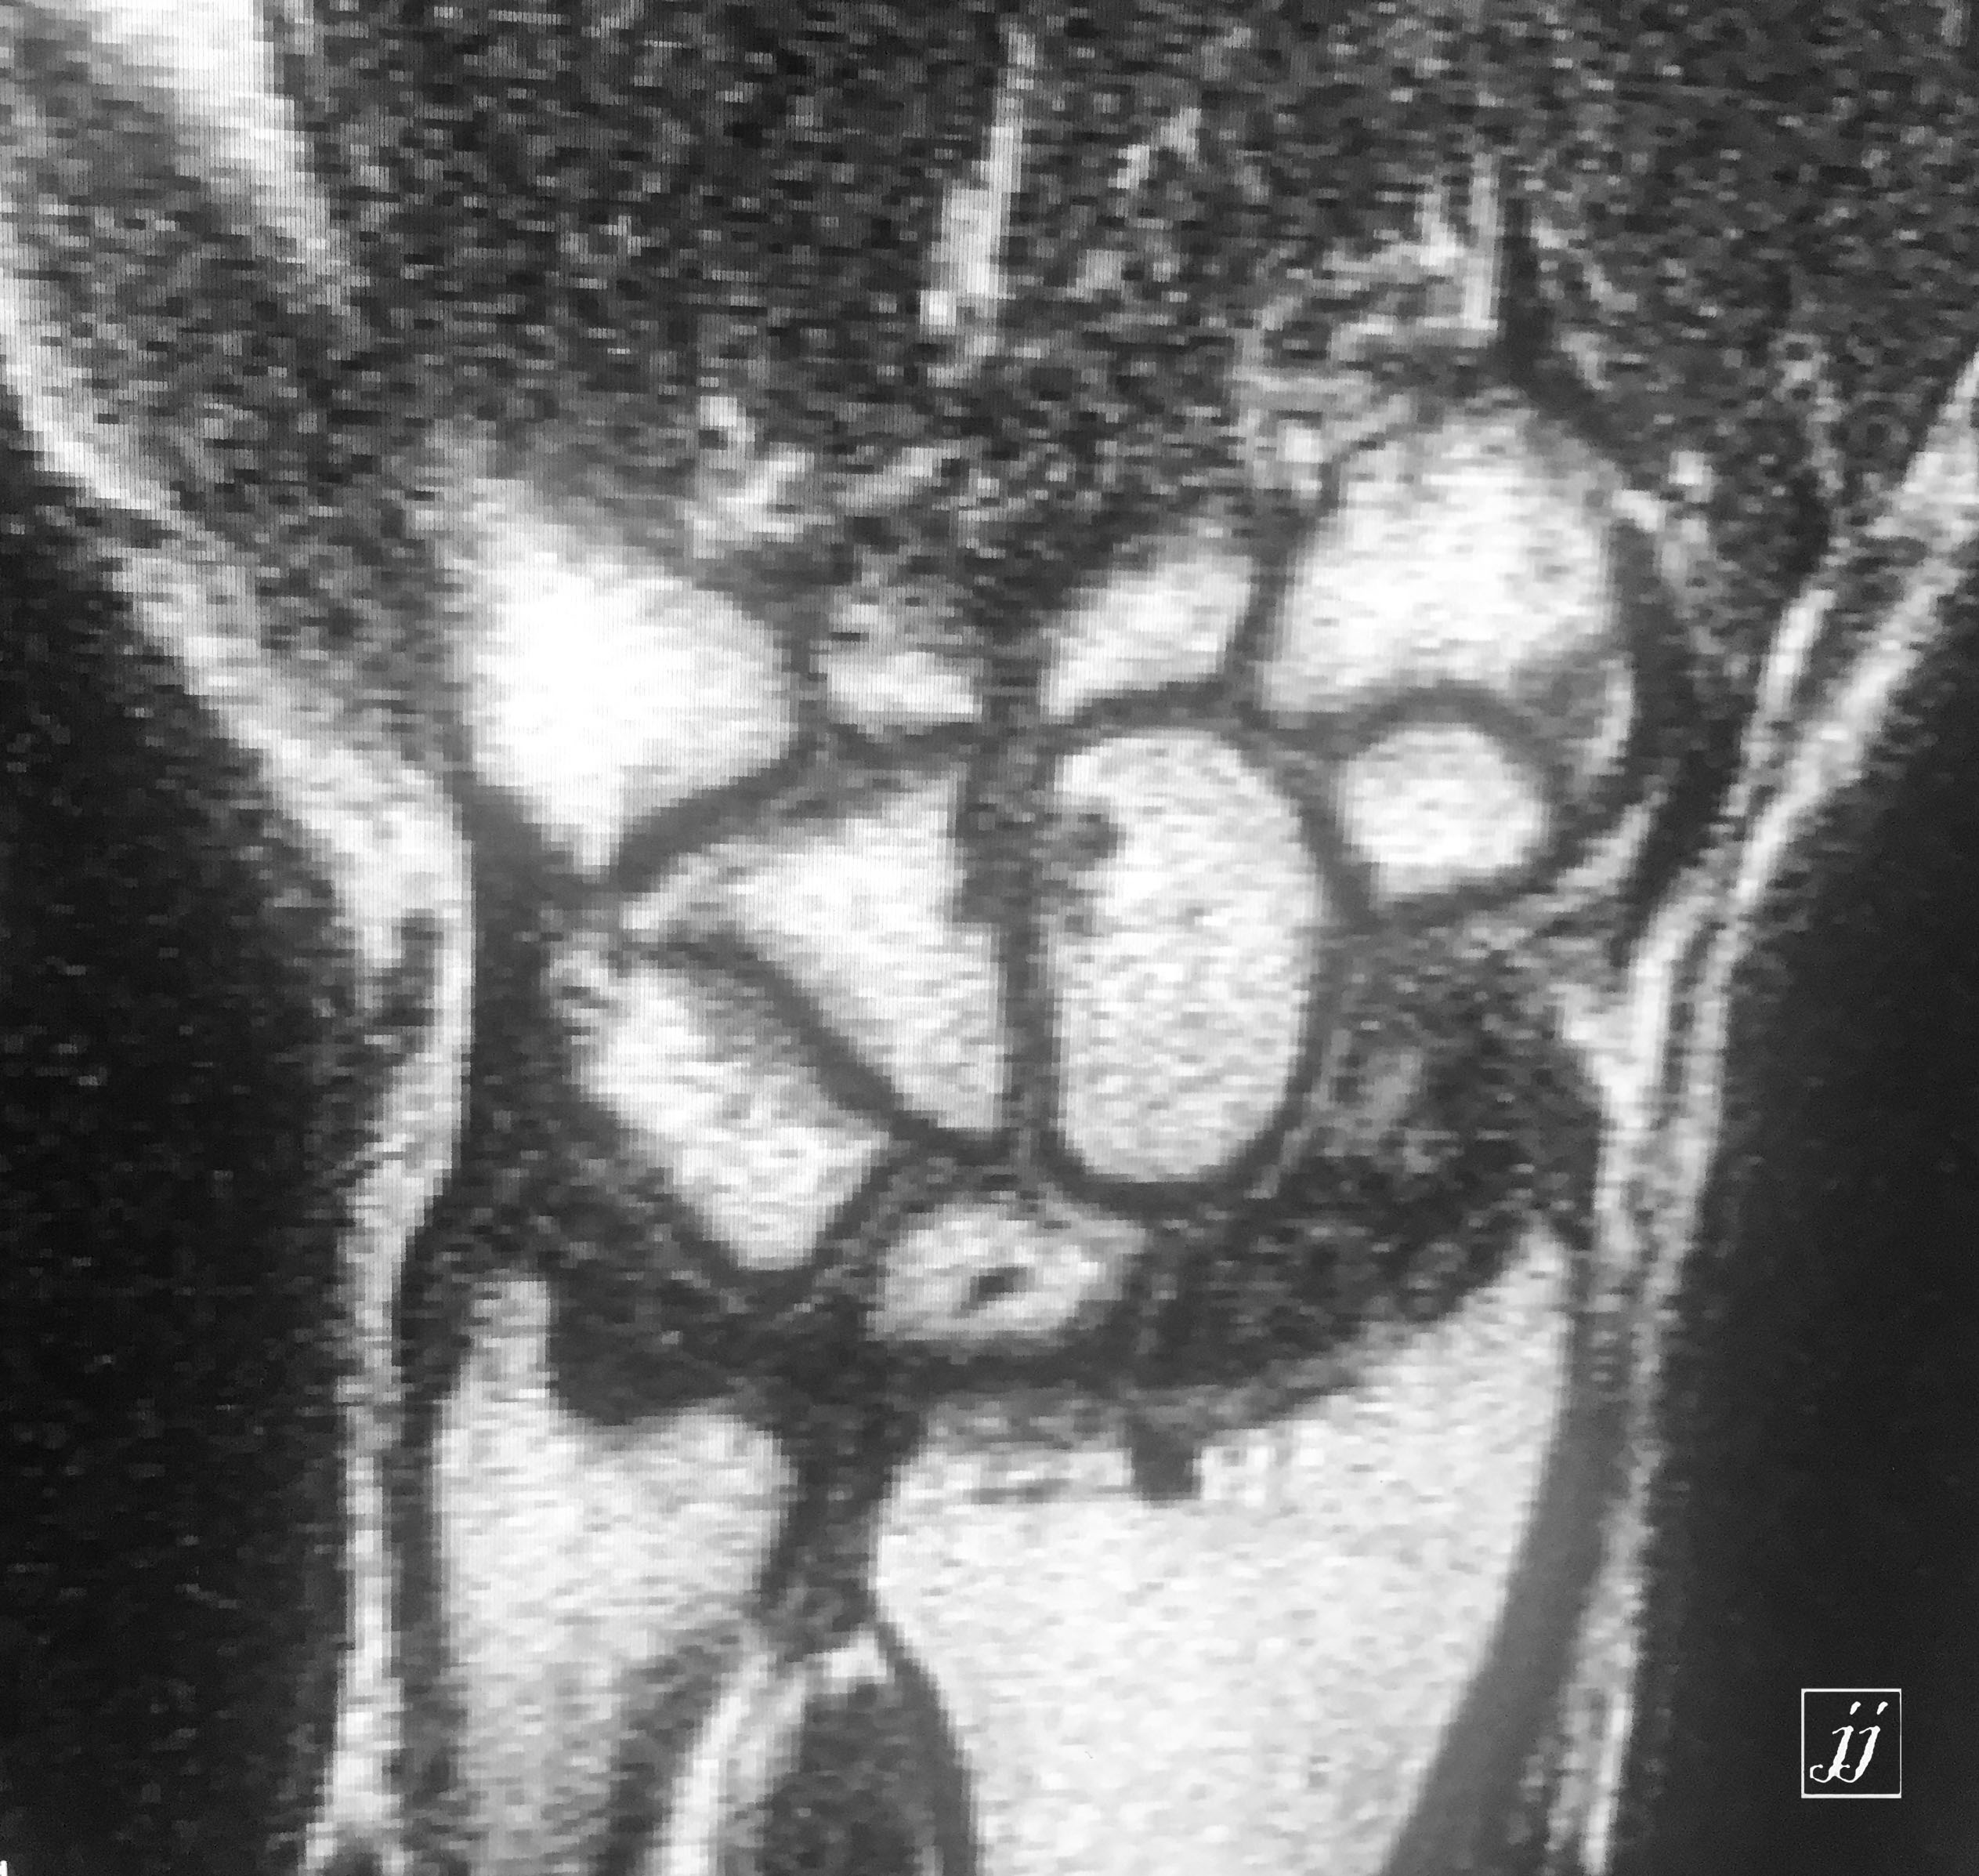

MSK- scaphoid fracture and proximal aVN (6)